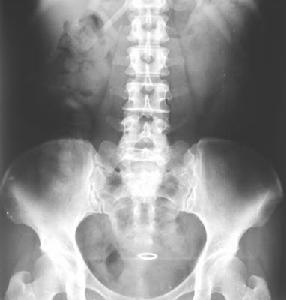

腹部照片沒有異常陰影。

腹部平片一般進行直立前後位或仰臥前後位攝片,根據需要,可加照直立側位、側臥水平位和仰臥水平側位照片。

異常結果: (1) 消化道腫瘤、炎症、外傷引起的消化道穿孔。 (2) 腸梗阻,並可鑑別是機械性腸梗阻還是麻痹性或是絞窄性腸梗阻。 (3) 腹膜炎。 (4) 腹腔膿腫。 (5) 腹腔腫塊。 (6) 消化道不透X線的結石。 (7) 腹部異常鈣化,如腹腔淋巴鈣化、肝包蟲病的鈣化。脾臟、腎和腎上腺、胰腺等臟器有腫瘤、結核、寄生蟲和炎症時均可發生鈣化,可根據鈣化的形態、部位作出診斷。 (8) 可觀察腹腔內臟器(肝腎脾等)的輪廓、位置和大小改變。例如肝臟腫瘤、包蟲病、囊腫等病變可使肝臟輪廓發生改變,並且其體積可以增大。腎盂積水、多囊腎和腎腫瘤可使腎影增大。一側腎發育不全和腎動脈狹窄可使腎影縮小。 (9) 可根據腰大肌影像是否腫大、模糊,腰椎有無側彎,椎體骨質有無破壞來診斷腰椎結核、腎周圍膿腫等。 (10) 腹部平片對診斷新生兒消化道畸形亦有很大的意義。如食管閉鎖時,胃腸道內可無氣體。幽門狹窄時,則胃擴大充氣,而腸管內氣體少或無氣體。先天性小腸狹窄時,閉鎖以上的腸管內充氣擴張並有液平面形成,而閉鎖以遠的腸管內無氣體。肛門閉鎖和胎便性腹膜炎都能在腹部平片上有所表現。 (11) 腹部平片可觀察胎兒的位置、形態、大小和數目。 (12) 可觀察金屬避孕環是否存在,及其位置和形態等。 需要檢查的人群:腹部經常有異常疼痛的人群,中老年人群。